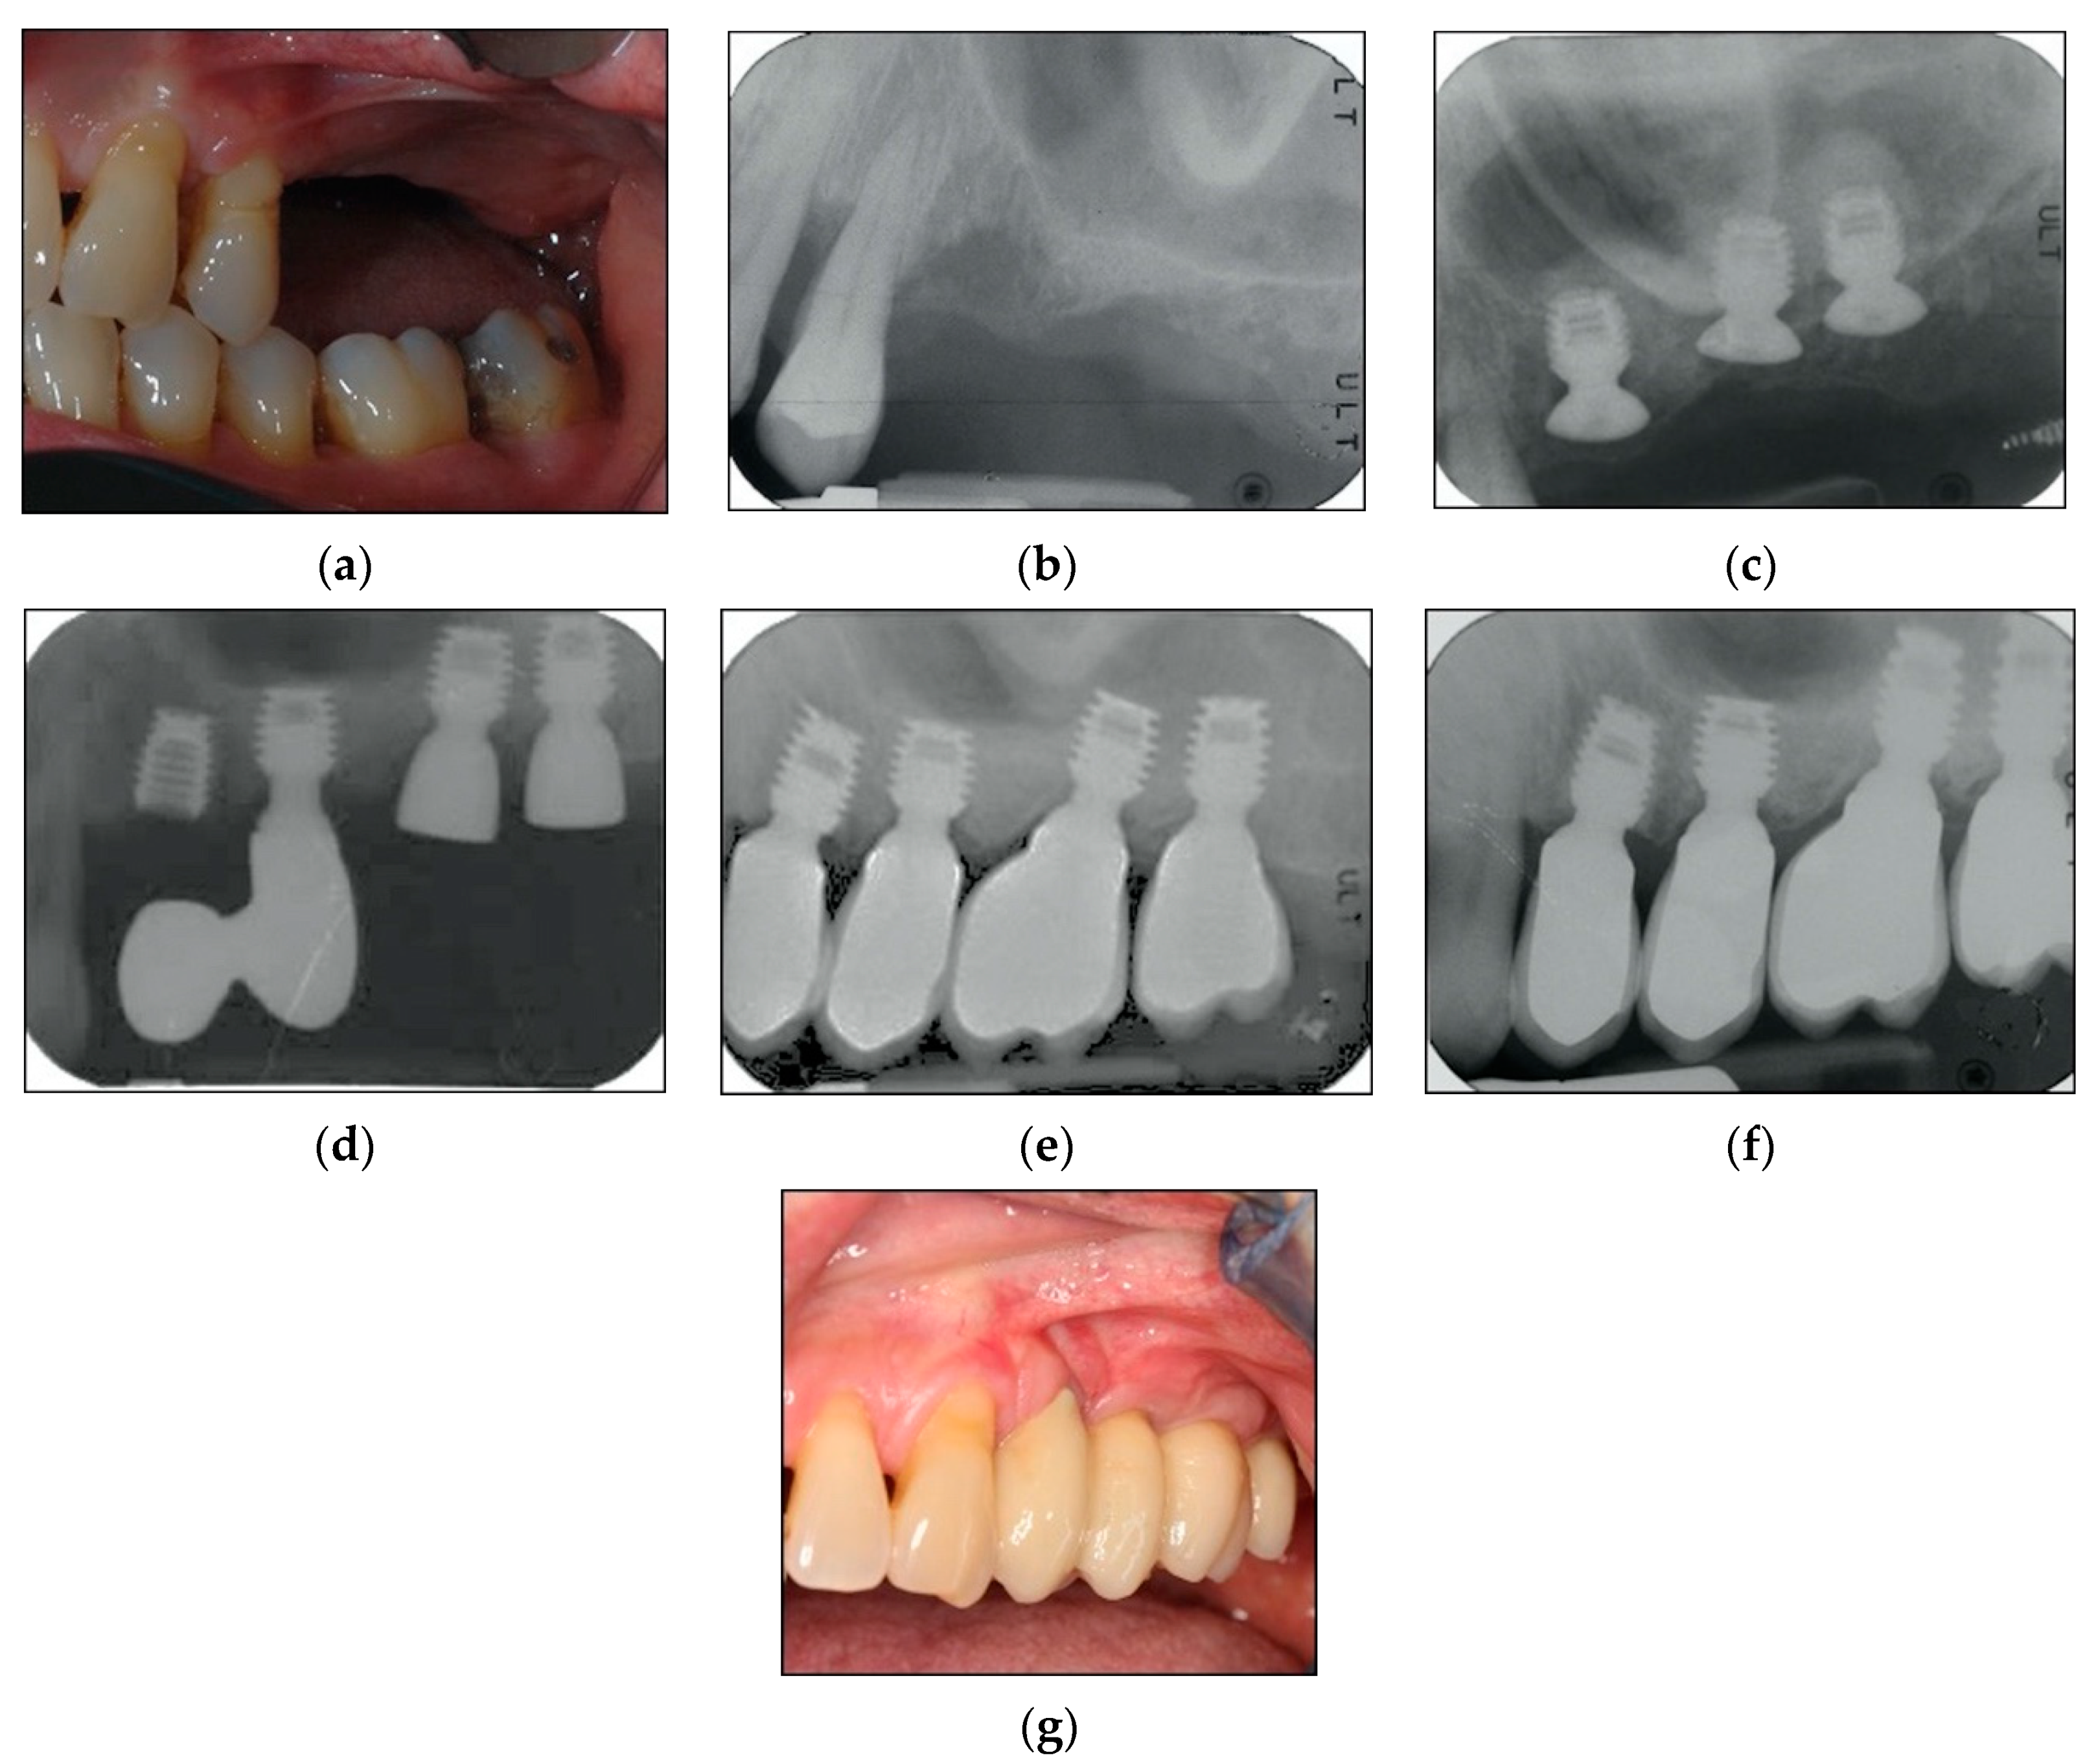

2.2. Surgical Protocol

2.3. Prosthetic Protocol and Follow-Up Evaluation